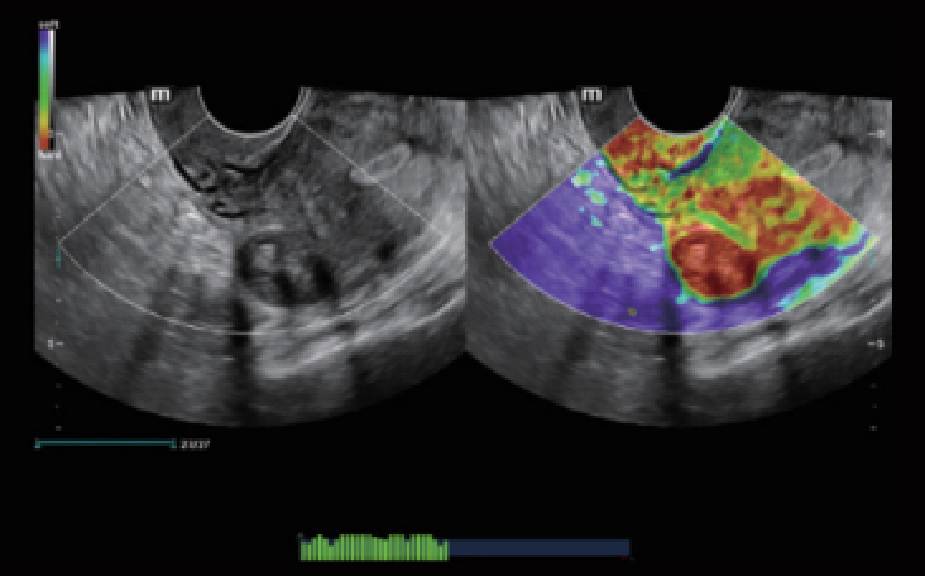

Full-stack oplossing aangedreven door ZST+

Het ZST+ platform is een buitengewone innovatie en revolutie in de wereld van ultrasound. Het transformeert ultrasoundgegevens van conventionele bundelvorming naar kanaalgegevensverwerking. Het overwint de traditionele afweging tussen ruimtelijke resolutie, temporele resolutie en weefseluniformiteit, en levert een uitzonderlijke beeldkwaliteit voor oneindige beeldvormingsoplossingen met non-stop verbeteringen.